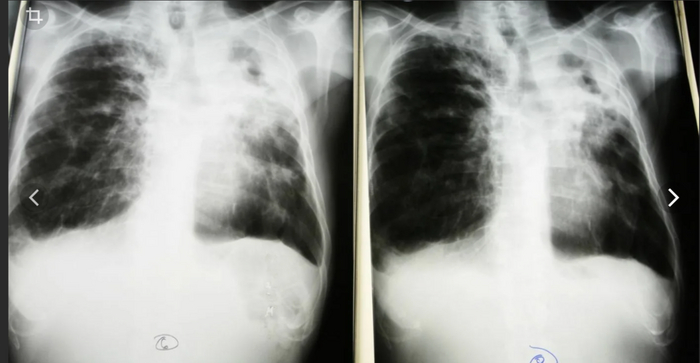

Продолжая свою серию постов о инфекционных заболеваниях, сегодня обращаем свое внимание на туберкулез.

Туберкулез – это инфекционное заболевание, которое преимущественно поражает органы дыхательной системы и вызывается определенной группой бактерий. Он передается через воздушно-капельный путь при кашле, чихании или выделении инфицированными людьми.

Диагностика.

Молекулярно-диагностические экспресс-тесты, такие как Xpert MTB/RIF Ultra и Truenat, рекомендуются Всемирной Организацией Здравоохранения (ВОЗ) в качестве первоначального диагностического теста для всех людей, у которых есть признаки и симптомы туберкулеза. Эти тесты обладают высокой точностью и значительно способствуют раннему обнаружению туберкулеза и случаев туберкулеза с лекарственной устойчивостью.

Для выявления инфекции также могут быть использованы кожная туберкулиновая проба (КТП) или анализ высвобождения гамма-интерферона (ИГРА).

Однако диагностирование туберкулеза с множественной лекарственной устойчивостью и других стойких форм туберкулеза, а также ВИЧ-ассоциированного туберкулеза представляет собой сложную и дорогостоящую задачу.

Симптоматика туберкулеза может различаться в зависимости от того, какая часть организма подвержена инфекции. Хотя заболевание чаще поражает легкие, оно также может распространиться на почки, мозг, спинной столб или кожу.

Диагноз, который мне назвал брат - милиарный туберкулез обоих легких, открытая форма. Струхнули все. 7,5 месяцев жить в тесном вагончике с туберкулезником, это вам не в тапки гадить. И все прошли медосмотр в одной частной клинике медосмотров.